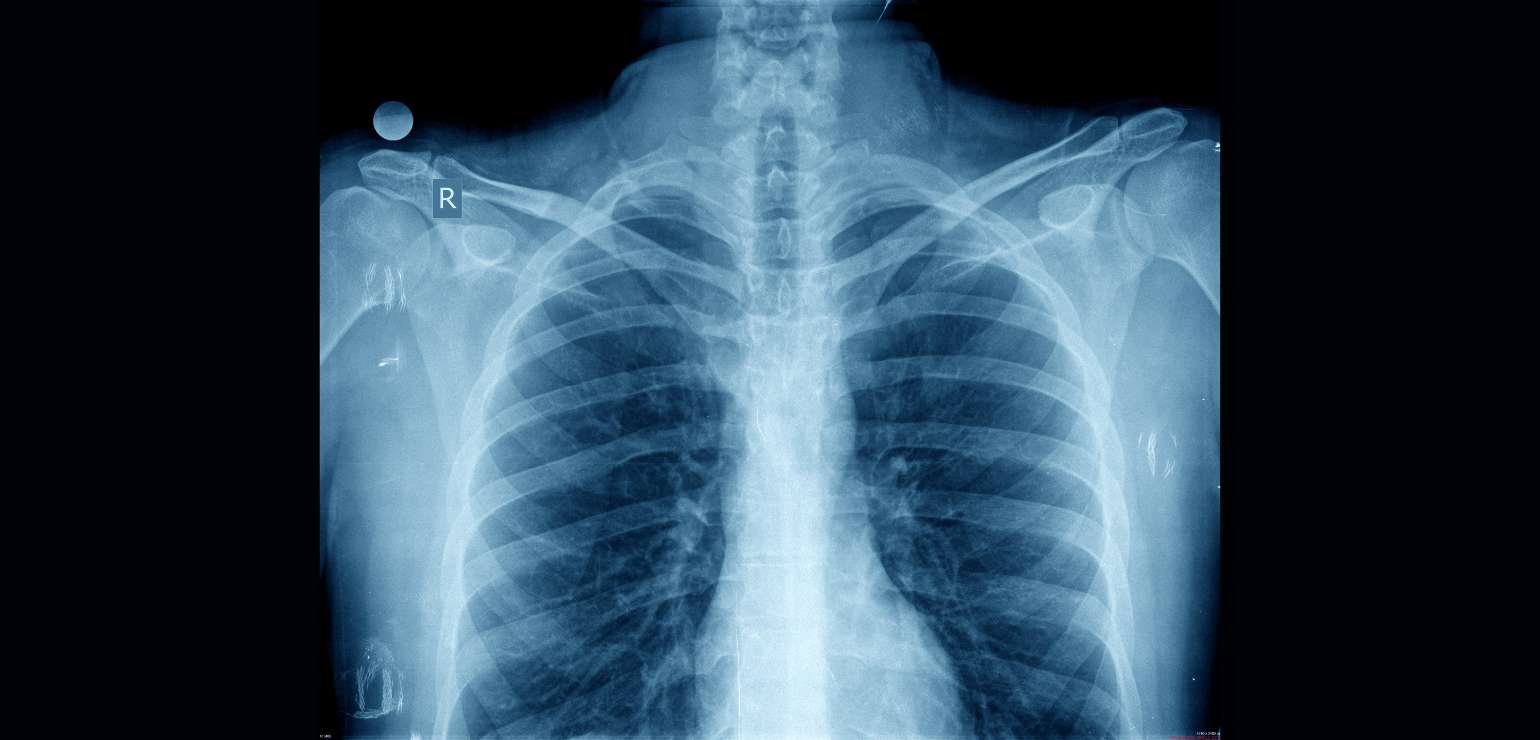

Chest X-ray

What is a Chest X-ray?

Chest x-ray is performed to get images of the chest area including lungs, heart and rib area. This determines the problems in the chest area at a very basic level making it the fastest way of diagnosing the issueHence it is mainly used for emergency diagnosis.